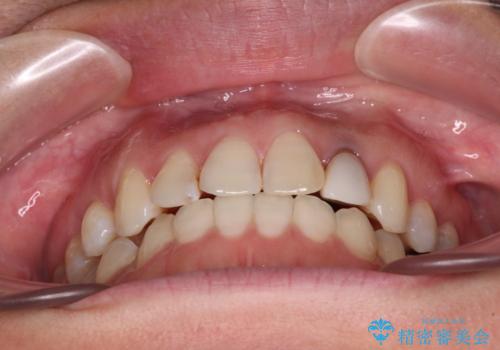

開咬と変色した前歯 インビザライン矯正とオールセラミッククラウン治療

- 前歯の開咬と失活により変色した前歯を気にして来院された患者様です。

開咬の治療は、前歯を閉じるように引っ張り出すよりも、上下臼歯を圧下(骨内にめり込ませる)させることで進める方が長期的に安定した歯列を維持できます。

インビザラインは臼歯の圧下を効果的に行えるため、インビザラインを用いて矯正治療を行うこととしました。

矯正治療が概ね終了した時点で前歯をオールセラミッククラウンにて補綴治療を行い、その後インビザラインにて細かい部分を仕上げていくことしました。